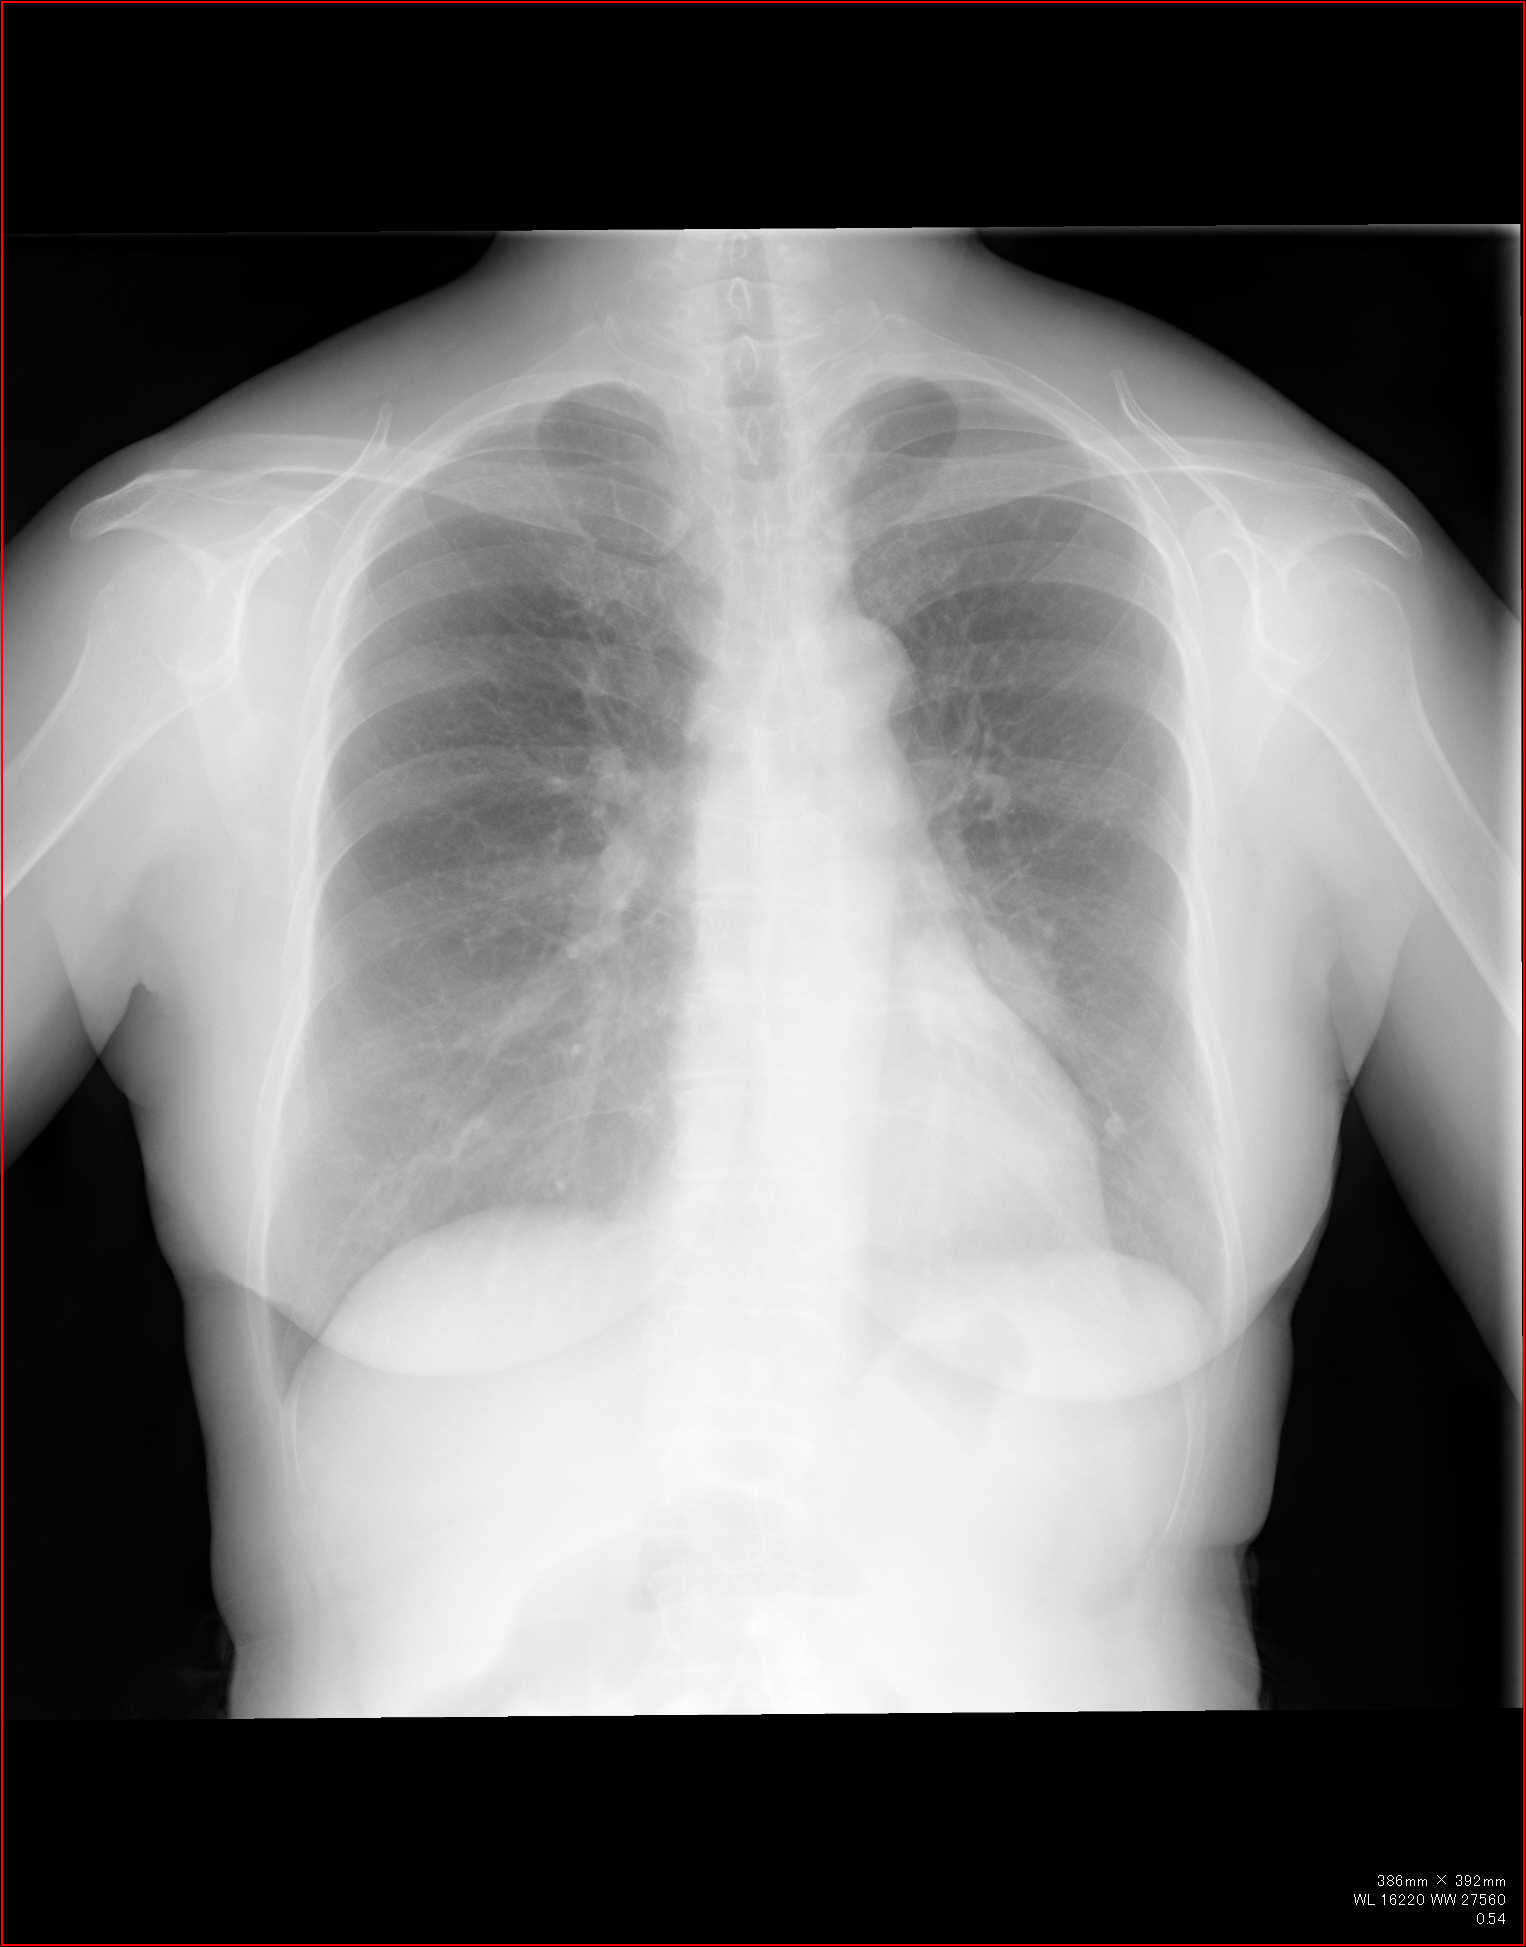

こちらを見て下さい。

わかりにくいかもしれませんが、このあたり。

気管が追いにくい、無くなっているようにも見えます。